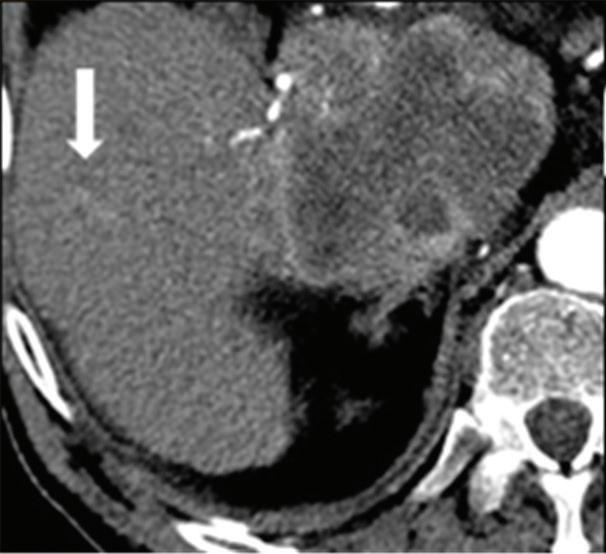

Renal and adrenal gland tumors. Contrast-enhanced-DECT images are particularly useful for the characterization of incidental renal or supra-renal lesions and for their follow-up, without the need of conventional unenhanced acquisition, translating into achieving a 30% mean dose savings for triphasic and up to 50% for biphasic renal protocols in daily clinical practice.17 It is also very useful in depicting hypervascular renal cell carcinoma metastasis in the liver or other sites, such as in the peritoneum and bowel wall (Figures 2 and 3).

Z effective

Spectral CT is able to generate Z effective images that show the mean atomic number of the material present in a voxel (Z effective values) and can be displayed as color coded overlay maps. Z effective images may be helpful to enhance the visual differences between different tissue types.46 Furthermore, due to the high atomic number of iodine compared to other tissues present in the human body, the Z effective images can highlight enhancing structures (Figures 2, 3, 4, and 5) and could be used for quantitative analysis to differentiate benign from malignant tumors or lymph nodes.16,45,47

Effectiveness of spectral CT imaging for detection of hypervascular liver metastases. A small hypervascular metastasis (arrow) from renal cell carcinoma. (a) Axial contrast-enhanced conventional CT image obtained in the arterial phase, corresponding (b) monoenergetic 50 keV, and (c) Z effective image.

Liver tumors. Use of low-monoenergetic images on late arterial phase improves the detection of hypervascular liver lesions (e.g., HCC in cirrhotic liver) (Figure 4).3,17,52,53 It also improves detection of hypovascular liver metastases on portal-venous-phase.54